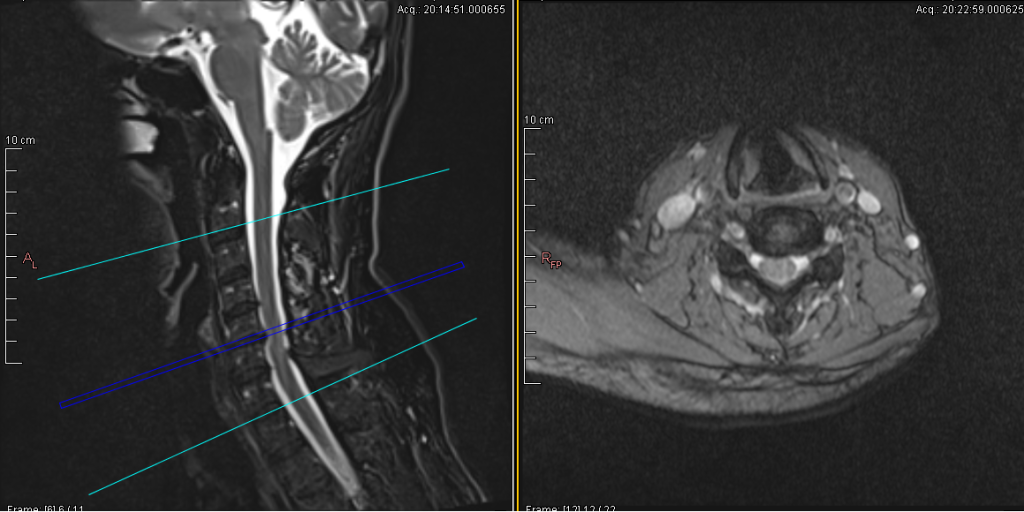

Contoh hasil MRI cervical

Prosedur Pemeriksaan MRI